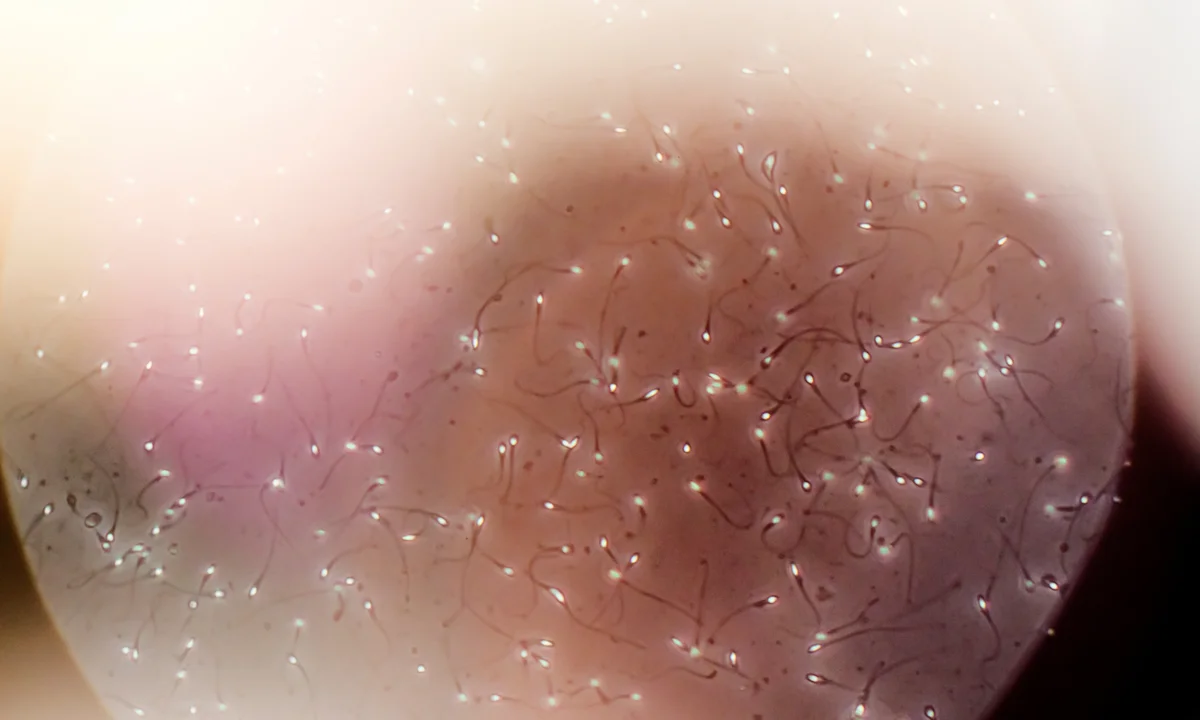

ஆண்கள் மத்தியில், உயர் தர விந்தணு கொண்டவர்கள் நீண்ட காலம் வாழ்கிறார்கள் என்று ஒரு ஆய்வு கூறுகிறது. அதாவது மிக உயர்ந்த மற்றும் மிக குறைந்த தரமான விந்தணுவை கொண்ட ஆண்களுக்கு இடையே உள்ள ஆயுட்கால வித்தியாசம் கிட்டத்தட்ட மூன்று ஆண்டுகள் ஆகும் என்றும் அந்த ஆய்வில் தெரிய வந்துள்ளது.

டேனிஷ் விஞ்ஞானிகள் கிட்டத்தட்ட 80,000 ஆண்களிடமிருந்து விந்தணு மாதிரிகளை பகுப்பாய்வு செய்தனர். ஒரு விந்து வெளியேற்றத்திற்கு 120 மில்லியனுக்கும் அதிகமான விந்தணுக்களை உற்பத்தி செய்தவர்கள், 5 மில்லியனுக்கும் குறைவாக உற்பத்தி செய்தவர்களை விட இரண்டு முதல் மூன்று ஆண்டுகள் நீண்ட காலம் வாழ்ந்ததாக கண்டறியப்பட்டது.

மிக உயர்ந்த தரமான விந்தணுவை கொண்ட ஆண்கள் சராசரியாக 80.3 ஆண்டுகள் வாழ்ந்தனர். அதேசமயம், மிகக் குறைந்த தரமான விந்தணுவை கொண்டவர்கள் சராசரியாக 77.6 ஆண்டுகள் வாழ்ந்ததாக ஆய்வாளர்கள் தெரிவித்தனர்.

“உண்மையில் விந்தணுவின் தரம் எவ்வளவு சிறப்பாக இருக்கிறதோ, அவ்வளவு நீண்ட காலம் உயிர்வாழ்கிறார்கள் என்பது தெளிவாகிறது,” என்பது இந்த ஆய்வில் இருந்து தெரிய வந்துள்ளது.

இந்த ஆய்வின் மூலம் விந்தணுவின் தரம் ஒரு ஆணின் ஒட்டுமொத்த ஆரோக்கியத்தையும், பிற்காலத்தில் மருத்துவ நிலைகளுக்கு ஆளாகும் வாய்ப்பையும் பிரதிபலிக்கிறது என்பதை காட்டுகிறது. ஆய்வாளர்கள் சோதித்த விந்தணு தரத்தின் ஒவ்வொரு அளவீட்டிலும், குறைந்த தரம் முன்கூட்டிய மரணத்துடன் தொடர்புடையதாக இருந்தது.

இந்த ஆய்வில் பங்கேற்ற ஆண்களுக்கு 1965 மற்றும் 2015 க்கு இடையில் விந்தணு பகுப்பாய்வு செய்யப்பட்டது. அவர்கள் முழுமையான சம்மதத்திர்கு பின்னரே இந்த சோதனைகள் மேற்கொள்ளப்பட்டன. விந்தணுவின் அளவு, விந்தணு செறிவு, விந்தணு வடிவம் மற்றும் நகரும் விந்தணுவின் விகிதம் ஆகியவற்றுக்காக மாதிரிகள் மதிப்பீடு செய்யப்பட்டன. சில ஆண்கள் விந்தணுவை உற்பத்தி செய்யாத நிலையில், மற்றவர்கள் மிக நல்ல விந்தணு தரத்தை கொண்டிருந்தனர்.